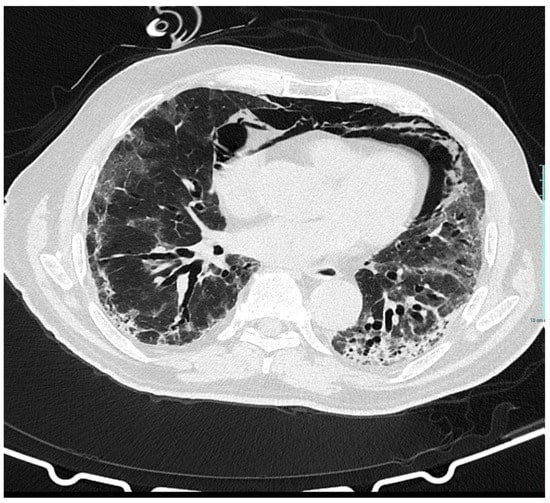

Pneumomediastinum and Pneumothorax as Relevant Complications of Sub-Intensive Care of Patients with COVID-19: Description of a Case Series

2. Description of Cases